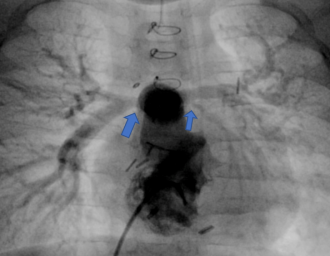

肺動脈統合術(unifocalizaton)術後 矢印の部分が狭窄病変

術後5ヵ月で肺動脈の狭窄に対してカテーテル治療を行った後の血管造影